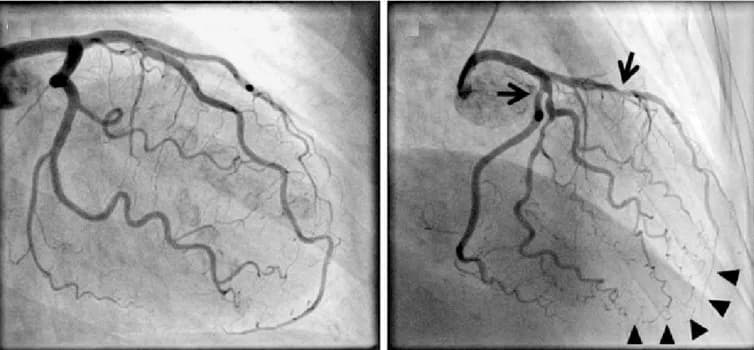

bệnh mạch vànhnhồi máu cơ timđặt stent động mạch vànhchụp động mạch vànhnong động mạch vành

Ưu điểm của kỹ thuật chụp, nong và đặt stent động mạch vành

Bệnh Mạch Vành: Giải Pháp Chụp, Nong và Đặt Stent Động Mạch Vành